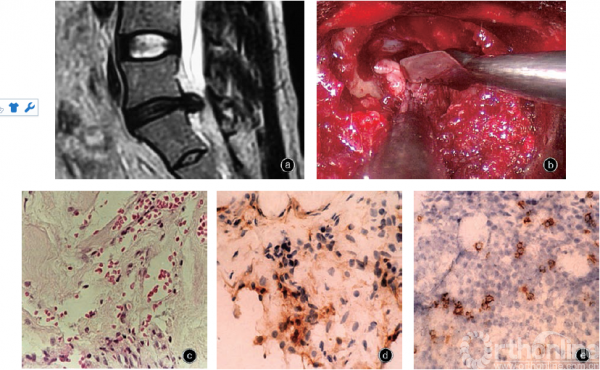

图1 男,20岁,椎间盘损伤疝出 a 矢状面MRI T2WI示L5S1椎间盘突出 b 后路脊柱内镜术中见突出物仅有薄层包膜包裹,触破包膜后有破碎的椎间盘髓核组织溢出(器械所指) c 疝出的椎间盘组织在光镜下有较多灶性炎细胞浸润及新生血管化,炎性反应明显HE染色×200 d, e 免疫组织化学检查显示疝出的椎间盘组织有CD4阳性T细胞(d)和CD8阳性T细胞(e)浸润 DAB染色×400

损伤疝出型相当于MacNab分类中的疝出、Spengler分类中的脱出和游离、AAOS& ISSLS分类中的脱出,同义语还有“extruded”、“prolapse”、“softherniation”、“true herniation”。此型椎间盘突出在术中可见病变表层纤维环和后纵韧带较薄,触之较软,有弹性,触压可诱发疼痛。切开表层组织后有成块破碎的椎间盘组织溢出,或很容易用髓核钳拉出,破碎的椎间盘物质孤立,与椎间盘母体分离或轻度粘连(图1)。该型突出病变部封闭者局部内压增高,可能与炎症和水肿有关。术中椎间盘造影时造影剂可向后延伸至后纵韧带,流入椎管内说明椎间盘破裂。外力损伤等因素可使病灶破裂,椎间盘物质溢出后可突破后纵韧带游离到椎管内。

(一)病理学改变

光学显微镜下疝出的椎间盘组织失去正常纤维环及髓核结构,纤维排列松散,组织破坏,灶性炎细胞浸润及血管化;其中肉芽组织、新生血管化明显高于退变突出型椎间盘组织,局部炎性反应更为明显。炎症反应和边缘血管化与损伤后修复性炎症改变有关。

免疫组织化学检查显示疝出的椎间盘组织有T淋巴细胞和巨噬细胞浸润,近边缘细胞浸润区可见在免疫应答中起重要作用的巨噬细胞:CD68和CD45RO阳性细胞,且有沿血管分布的趋势;CD4 阳性T细胞(delayedtype hypersensitivity Tlymphoctye,TDTH)和CD8阳性T细胞(cytotoxicT lymphoctye,TC)的阳性率也高于退变突出型椎间盘组织。IgG和IgM免疫荧光标记在炎性细胞浸润区可见较多颗粒或条带状黄绿色荧光反应带;外周血IgG和IgM水平高于退变突出型患者,而IgA、补体C3和循环免疫复合物水平与退变突出型无明显差异。另外,损伤疝出型椎间盘组织中IL-7阳性细胞数及IL-7mRNA的表达量均明显高于退变突出型椎间盘。

因此,损伤疝出型椎间盘突出的病理实质为椎间盘退变和损伤疝出及炎症修复过程,T淋巴细胞浸润和免疫球蛋白IgG、IgM沉积是在损伤基础上的自身免疫反应,进一步加重了组织损伤,使髓核组织破碎溶解、内压增高,最终破碎的椎间盘组织与主体分离并向椎管内突入。